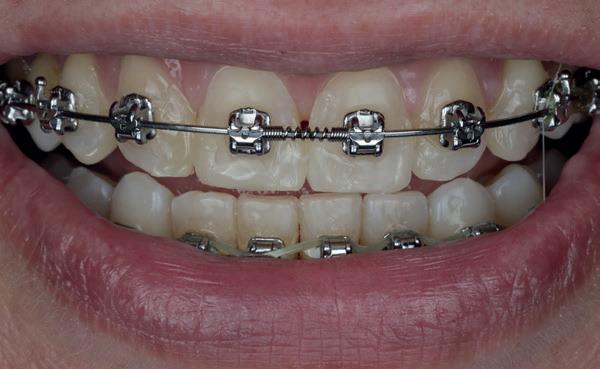

Op 16-jarige leeftijd werd de patiënt door haar behandelend orthodontist naar de auteur verwezen voor een restauratieve oplossing voor de afwezige 11 en 21. In de tussenliggende periode had patiënt een retainer gedragen met twee kunststof tanden (afbeelding 1). Zowel de patiënt als haar moeder hadden een sterke voorkeur voor een implantaat gedragen vaste oplossing. Gezien haar jonge leeftijd was dit echter nog geen optie, omdat er nog verticale groei te verwachten viel. Implanteren op jonge leeftijd – dat wil zeggen vóór het 21e levensjaar – kan resulteren in een infrapositie van het implantaat, omdat de rest van het gebit nog verticaal kan doorgroeien.

Middels shared decision making werd het volgende plan overeengekomen: eerst zou er een etsbrug met vleugels op de 12 en 22 worden vervaardigd, om op 21-jarige leeftijd verder te gaan met implantologie.

Bij klinisch en röntgenologisch onderzoek viel echter op dat radix van de 12 en 22 een convergerende (de radices staan dan naar mesiaal en naar elkaar toe) in plaats van divergerende (radices staan dan van elkaar af) stand had. Door deze convergerende stand van de radices was er in mesio-distale zin geen ruimte voor twee implantaten ter plaatse van de 11 en 21. Er werd daarom besloten, in tegenzin

1. Retainer met twee frontelementen

2. OPT radices 12 en 22 convergeren

3. Vaste apparatuur voor torque 12 en 22

4. OPT radices 12 en 22 divergeren na orthodontische behandeling

van de patiënt, om eerst weer vaste apparatuur terug te plaatsen om de radices in een divergerende stand te plaatsen. Gelukkig verliep deze behandeling voorspoedig. (afbeelding 2 -4). Het volgende behandelplan werd gemaakt: